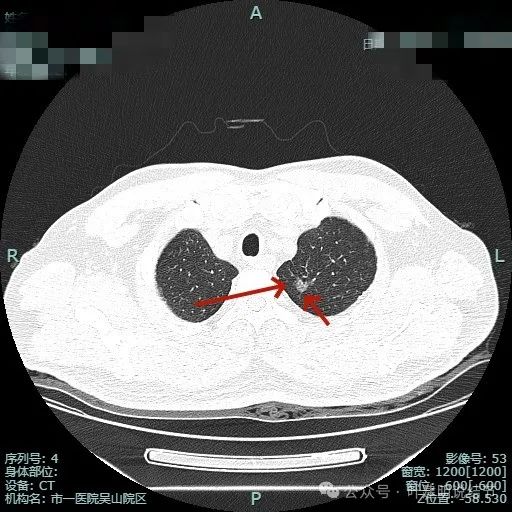

先看非薄层影像:

密度不纯,有明显分叶。

有血管异常增粗与进入,边缘有细毛刺征。